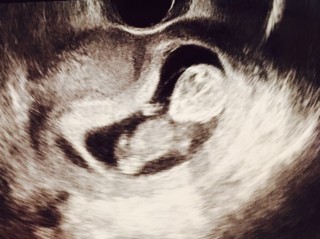

可愛いくて仕方ないです(*´ω`*) 4.3cmとのことでした! 先生から週数通りの順調ですとのこと。 4週間後が待ち遠しいです♪ 赤ちゃんは起きていて動き回っていました(*´ω`*)